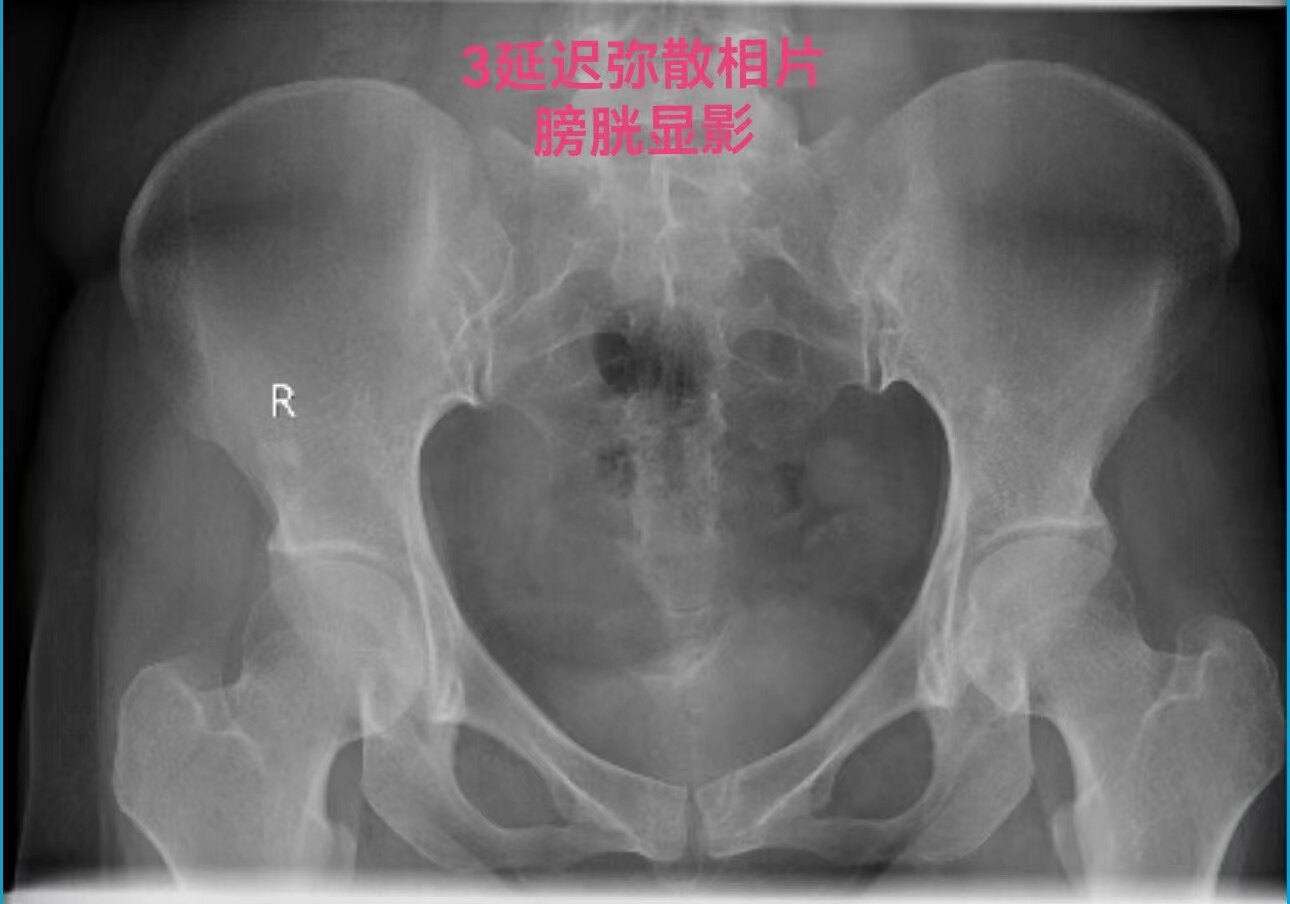

在做子宫输卵管造影检查时:当所用造影剂为碘油,出现静脉和淋巴管逆流时,立即停止造影检查是对的。因为碘油和血液不能相容混合一起,碘油会形成油栓。因此,当碘油进入静脉和淋巴管后会进入下腔静脉,进入右心房,进而进入肺动脉,形成肺栓塞,可危机被检查者生命安全。但是,当所用造影剂为碘水,出现静脉和淋巴管逆流时,可以继续造影检查,直至满足临床诊断后再结束检查。因为碘水和血液可以相容会混合一起,碘水逆流进入静脉和淋巴是安全的。大家好多做过CT增强检查,成年人一般需要用高压注射器要向静脉内快速注入100毫升碘水进行检查,都是安全的。造影注入10毫升左右碘水,即使都进入静脉也没事。这二例,一例碘油造影是一大学附属妇产医院做放射科的,该立即停止造影却没有停止。万幸,逆流进入静脉的碘油少,没有造成严重后果。另外一例碘水造影是一省妇幼保健院放射科做的,不该停止造影检查,反而停止造影检查,未能完成检查,不能给正确诊断。

第一例碘油造影图和报告单